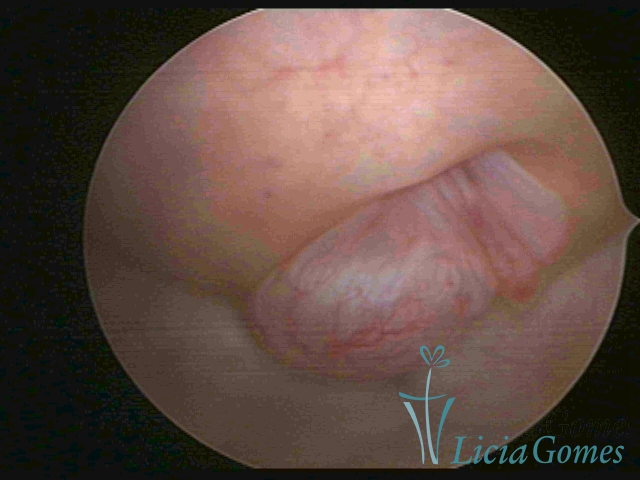

PÓLIPOS ENDOCERVICAIS

São tumores benignos, resultantes da proliferação focal reativa aos processos inflamatórios ou à situações de hiperestrogenismo, e podem ter sésseis (com a base de implantação larga) ou pediculados do epitélio.